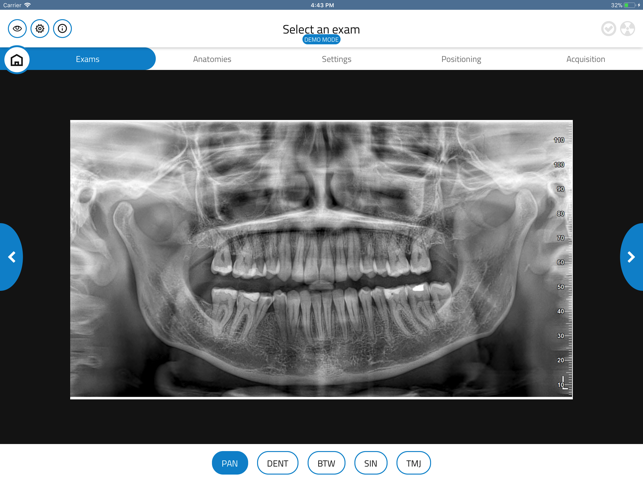

GiANO HR is a highly advanced dental equipment by NewTom, with panoramic, ceph and CBCT capabilities. NewTom Control Pad allows GiANO HR users to connect via Wi-Fi to the equipment, browse the diagnostic programs available, select an imaging modality and a region of interest before performing a radiographic examination.

NewTom Control Pad does not replace any PC workstation, where NewTom NNT imaging software will process and store the radiographic data. Nevertheless, NewTom Control Pad provides quick and easy previewing of 2D radiographs acquired, with image enhancement such as brightness, contrast and gamma correction, as well as e-mailing of 2D images to a preferred recipient.